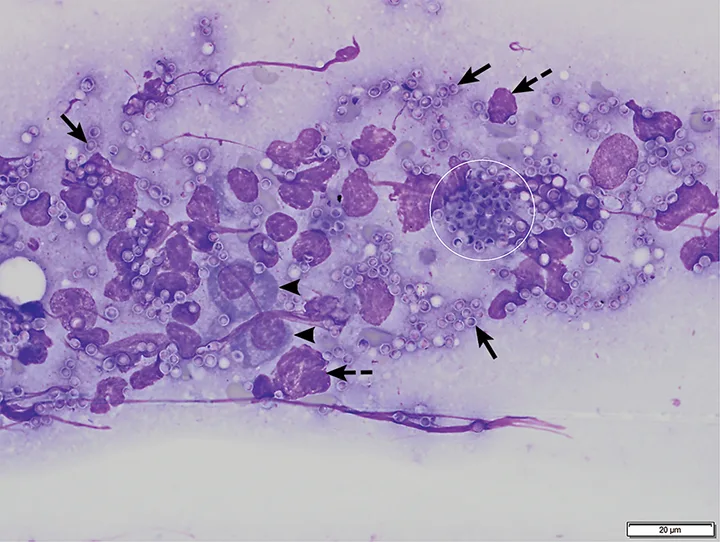

Featured Image

FIGURE 2

Bone marrow aspirate from a cat with pancytopenia. H capsulatum yeast structures are seen extracellularly (arrows) and intracellularly within a macrophage (circle). Plasma cells (arrowheads) and nuclear material from lysed cells (dashed arrows) are also present. Modified Wright’s stain, 1000×. Scale bar = 20 microns

Bone marrow cytology of this cat (Figures 1 and 2) showed no bone marrow particles, rare marrow hematopoietic precursor cells (ie, megakaryocytes, myeloid and erythroid cells), and occasional plasma cells. Macrophages were markedly increased. Numerous round-to-oval yeast bodies measuring 2 to 4 µm in diameter were seen extracellularly and inside macrophages. The organisms had a thin outer halo with an eccentrically placed, basophilic, crescent-shaped nucleus.